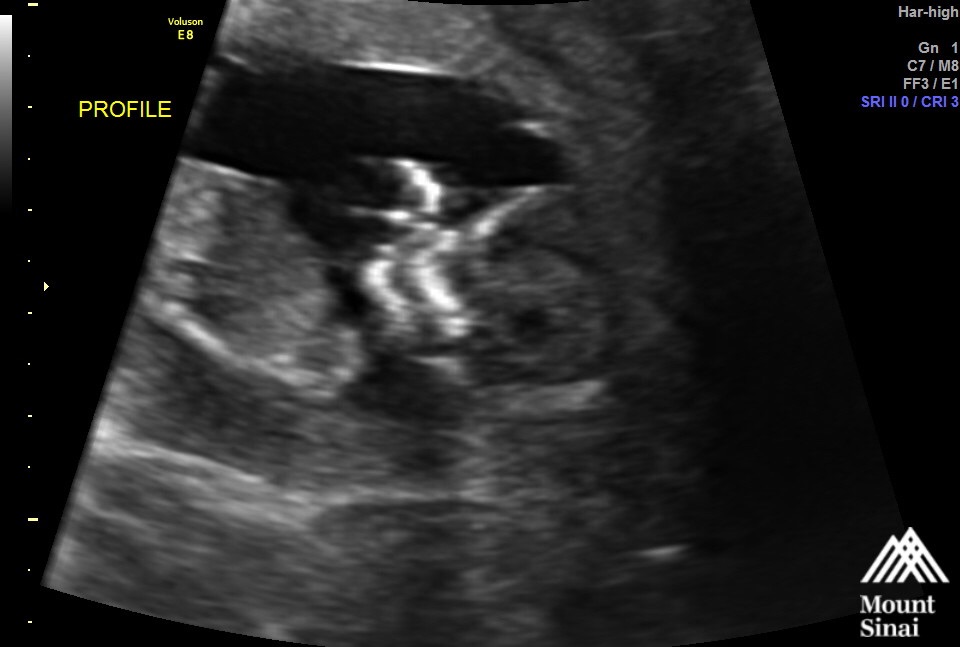

Our little one at 13 weeks 1 day! I didn't know you could have Braxton Hicks contractions this early - but apparently I was having one and it left baby a little squished and made it hard to get a good pic. Tech tried her best though! Loved seeing baby actually looking like a baby (instead of just a peanut) these days